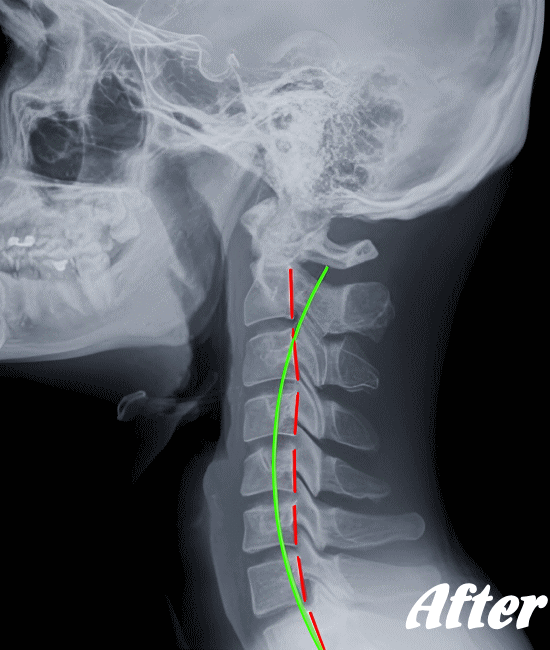

HALOカイロプラクティック☆平和島整体院では、骨盤(仙腸関節)から背骨(腰椎、胸椎、頸椎)、肋骨(肋椎関節)、肩甲骨(肩甲胸郭関節)などを調整し緩めることで、首(頚椎)にかかる負担を取り除き、可動域を良くして痛みを解消していきます。

首や肩周りの症状では、肩甲胸郭関節(肩甲骨周辺)を調整することは必須です。